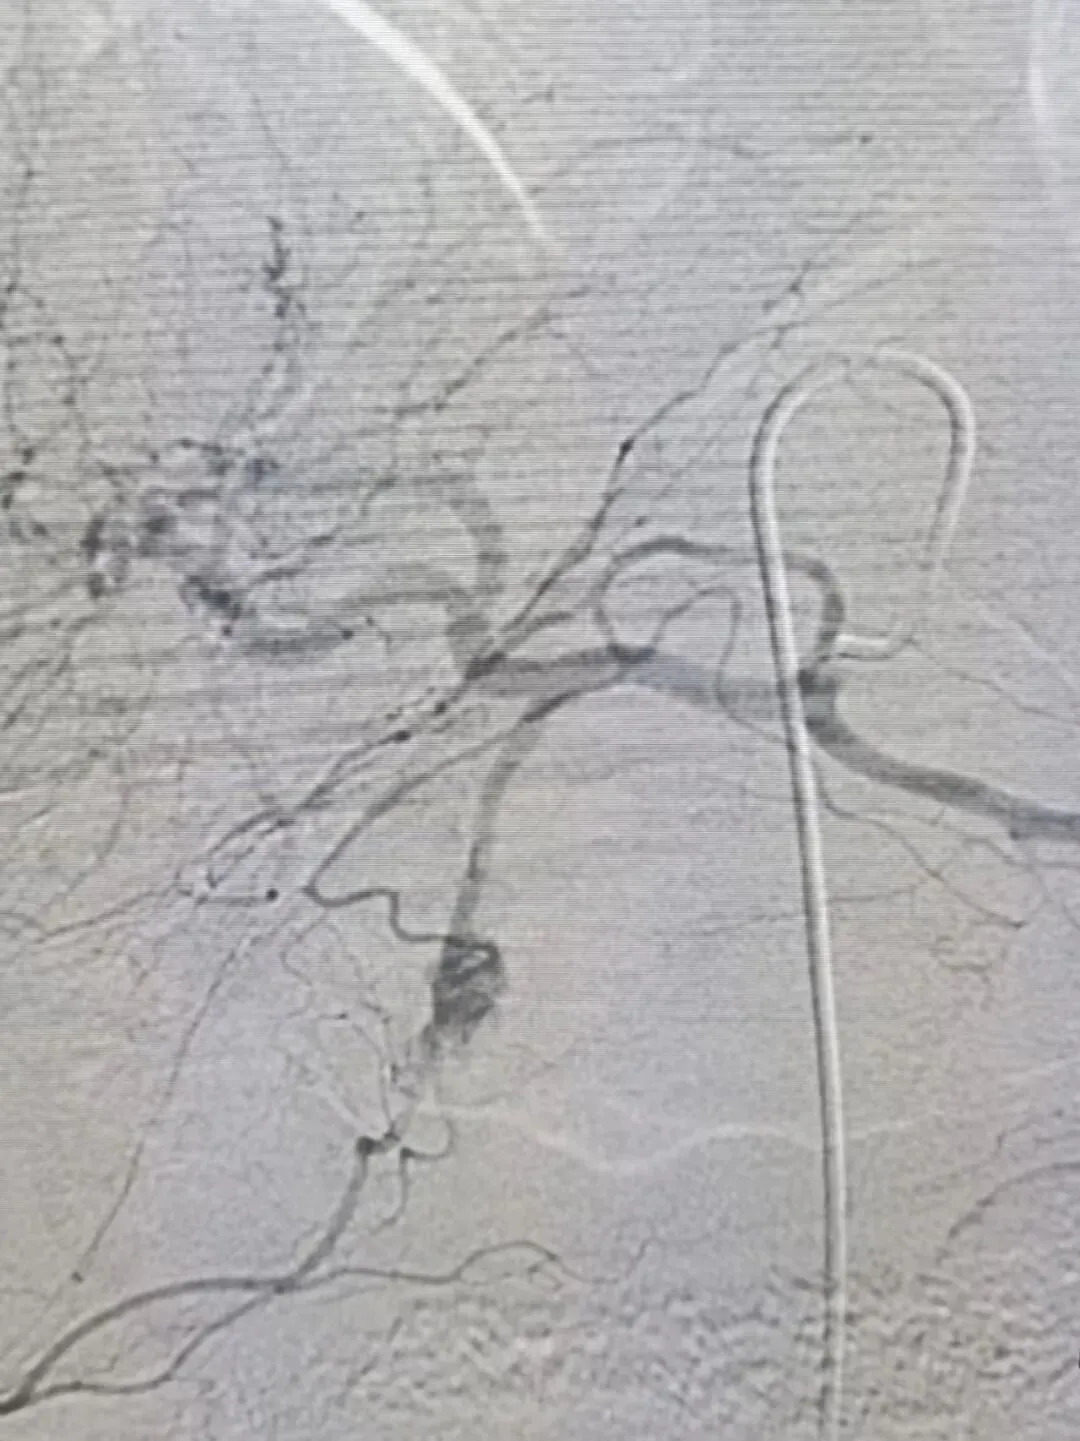

在介入治疗科崔凯主任团队的带领下,抢救团队迅速行动。术中,患者再次呕血约1000ml,血压一度跌至50/30mmHg,几度意识丧失,情况极其凶险。通过血管造影,清晰显示出血来源于胃左动脉远端活动性出血。团队果断决策,在X线引导下超选择性插管至目标血管,先后推注明胶海绵混合液及置入弹簧圈进行栓塞。随着栓塞完成,复查造影确认出血动脉已被成功封堵,活动性出血停止。手术历时一个多小时,成功将患者从生死边缘拉回。

图文/崔凯 李侠